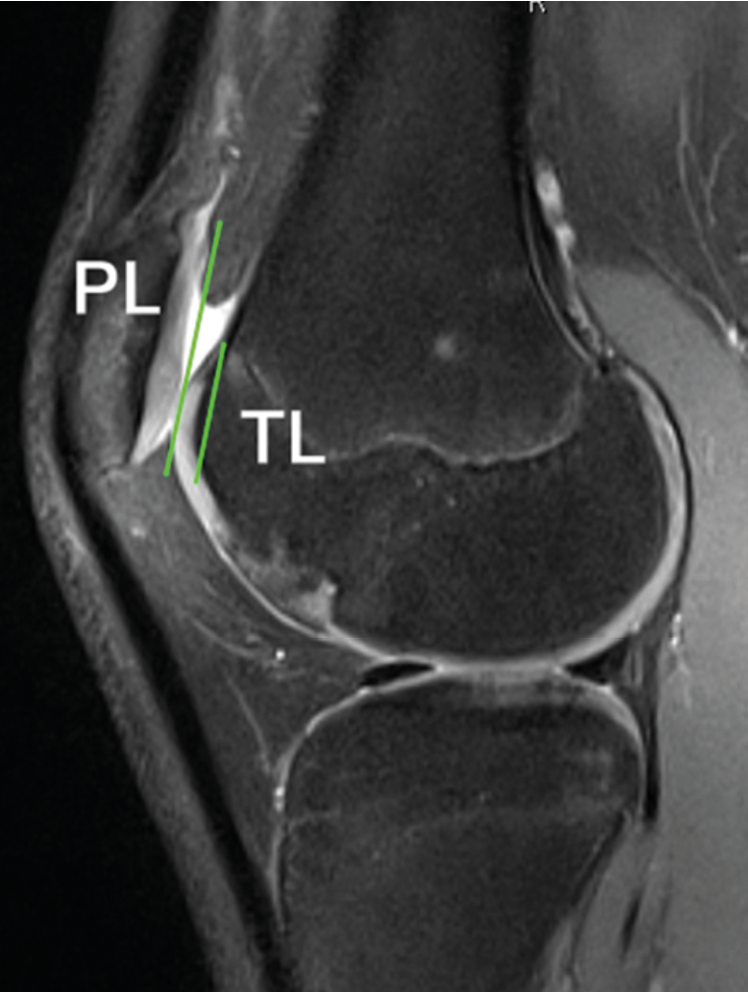

It can also be used to assess patellofemoral congruence by measuring the sagittal engagement index described by Dejour et al. in 2013 (Fig. 3).[17] D. Dejour, P. Ferrua, P.G. Ntagiopoulos, C. Radier, C. Hulet, F. Rémy, J. Chouteau, F. Chotel, P. Boisrenoult, A. Sebilo, S. Guilbert, D. Bertin, F.-P. Ehkirch, V. Chassaing. The introduction of a new MRI index to evaluate sagittal patellofemoral engagement. Orthop Traumatol Surg Res. 2013 Dec;99(8 Suppl):S391-8. This will reveal any functional high-riding patella with lack of engagement, despite a normal Caton-Deschamps score.

These 3D results (CT scan or MRI) can also help evaluate the position of the patella in the axial plane by measuring the TT-TG distance and the transverse engagement index. Lack of axial engagement is more commonly associated with objective instability and therefore beyond the scope of this article.